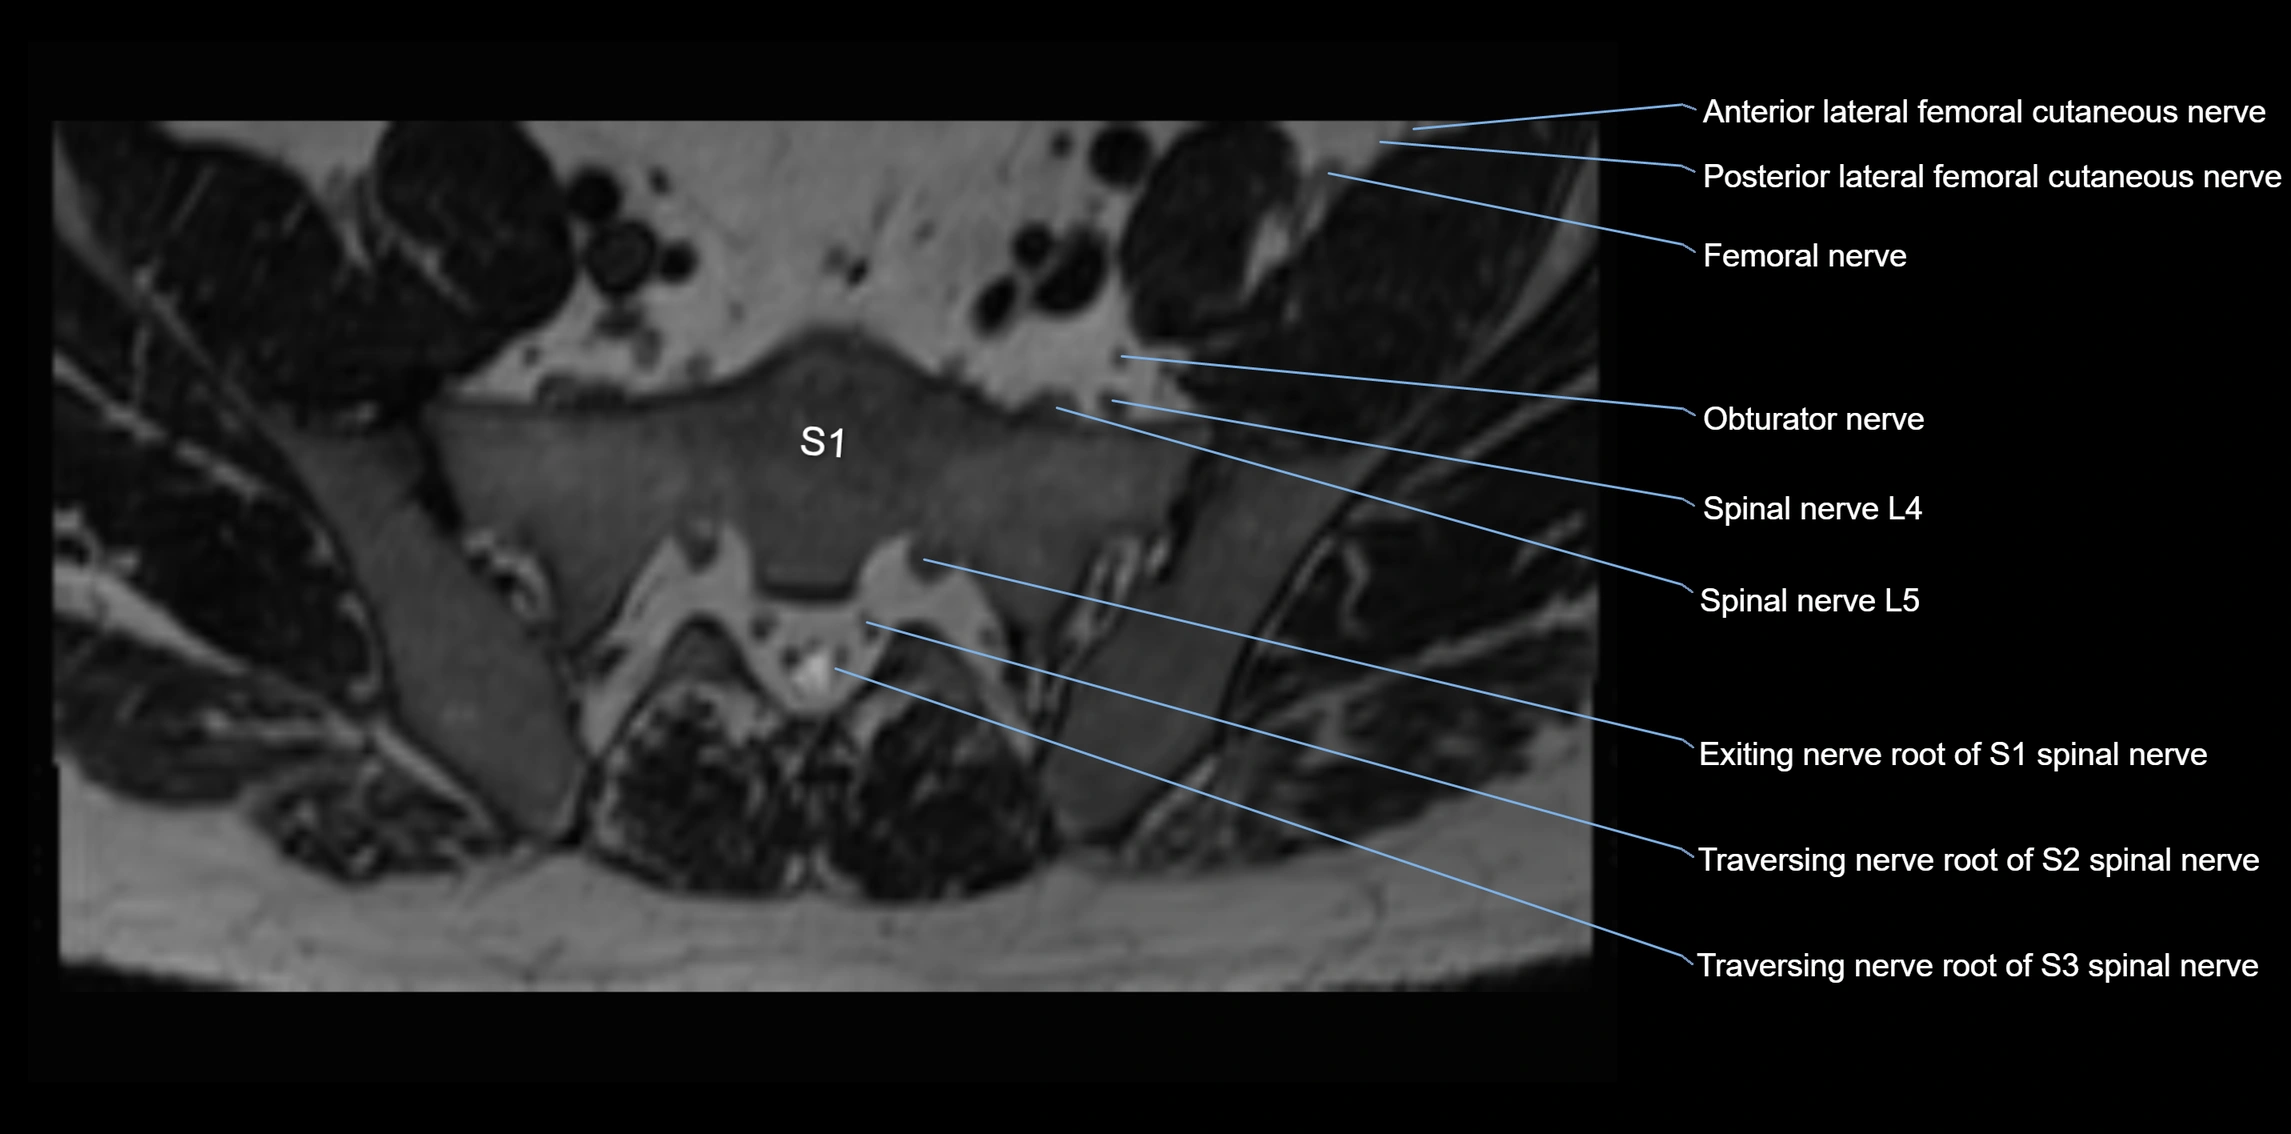

MRI Appearance

T1-weighted images:

• Nerve appears as a very thin low-to-intermediate signal intensity structure

• Surrounded by bright fat, aiding visualization

T2-weighted images:

• Nerve shows intermediate to mildly hyperintense signal compared to muscle

• Pathological involvement appears brighter

3D T2 SPACE / CISS:

• Nerve appears intermediate to mildly hyperintense compared to muscle

• Surrounded by bright fat or CSF, improving visualization

• Best sequence for mapping small pelvic nerves such as the anococcygeal